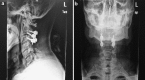

Methods: A 49-year-old Chinese male presented with a progressive cervical myelopathy (C-JOA score 11 immediately pre-op). Segmental OPLL at the C2-3 disk space was visible, together with invagination of the bilaterally hypoplastic C2 lamina into the spinal canal. Signal abnormalities of the spinal cord were evident on both T1 and T2 sequences.

Results: The patient underwent a posterior decompression and instrumented fusion at C2-3 using pars screws at C2 and lateral mass screws at C3. Following surgery there was a rapid and significant improvement in the neurological symptoms, with the C-JOA score improving to 14 at final follow-up. A successful fusion was evident.